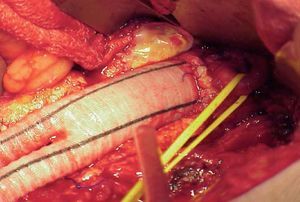

Cirugía de revascularización. La afectación difusa, extensa se trata de forma óptima habitualmente mediante el implante de una prótesis aórtica unifemoral o bifemoral (figs. 5 y 6). Se trata de una técnica de efectos conocidos, bien sistematizada y que ofrece unos resultados en términos de permeabilidad superiores al 85 y el 80% al cabo de 5 y 10 años, con cifras de mortalidad operatoria inferiores al 5%4. Sin embargo, es una cirugía arterial mayor y precisa cuantificar el riesgo quirúrgico para seleccionar a los candidatos más adecuados. En aquellos pacientes de alto riesgo o con un abdomen hostil (múltiples reintervenciones, radioterapia previa, infección activa, etc.) la intervención se realiza mediante las técnicas denominadas «extraanatómicas», que permiten la revascularización de las extremidades por trayectos no anatómicos, y con una menor agresión. Los más utilizados son la cirugía de derivación axilounifemoral o bifemoral, y la femoro-femoral. Ambos tipos de cirugías de derivación se tunelizan por vía subcutánea, la primera por la región lateral del tórax y el abdomen, y la segunda por la región suprapúbica. Pueden realizarse con anestesia locorregional. Las cifras de permeabilidad de las cirugías de derivación extraanatómicas son inferiores, con oscilaciones entre el 40 y el 70% a los 5 años, según la indicación clínica4. Por esta razón, raras veces se indican en ausencia de isquemia crítica.

Fig. 6. Imagen de una prótesis de Dacron con anastomosis infrarrenal. Control de arteria renal izquierda con cinta elástica.

Cuando la obstrucción se extiende a la poplítea infragenicular y los vasos distales, la revascularización se realiza mediante una cirugía de derivación cuya anastomosis distal se efectúa en el vaso distal en mejor estado que asegure la perfusión directa al pie (fig. 8). En este caso nos referimos a una cirugía de revascularización femorodistal, politeodistal o tibiotibial, según la localización de la anastomosis proximal. En general, estas derivaciones ofrecen tasas de permeabilidad similares a las obtenidas con las derivaciones a poplítea, siempre que se utilice material autólogo, pero muy inferiores cuando se u tilizan prótesis. No obstante, las tasas de salvación de la extremidad superan el 70% a los 5 años.

Fig. 8. Cirugía de derivación venosa femoroperoneal. Control arteriográfico.